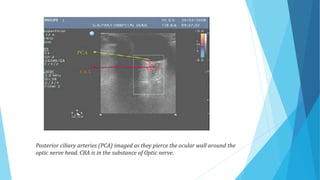

Posterior ciliary arteries (PCA) imaged as they pierce the ocular wall around the

optic nerve head. CRA is in the substance of Optic nerve.